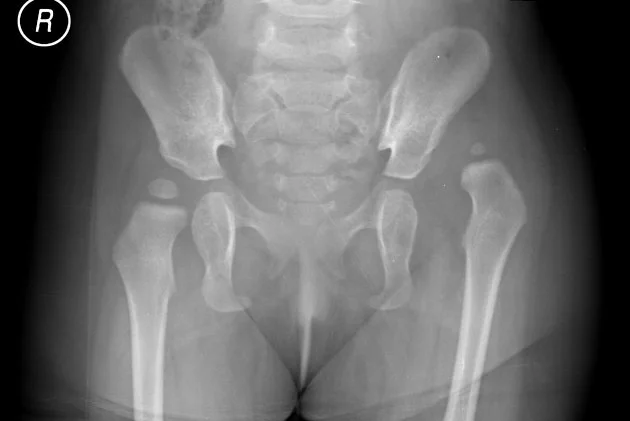

• Radiographs (X-rays): Used after 4-6 months of age when the femoral head begins to ossify.

Developmental Dysplasia of the Hip (DDH) is a spectrum of conditions related to the abnormal development of the hip joint in infants and young children. It ranges from mild acetabular dysplasia to complete dislocation of the hip.